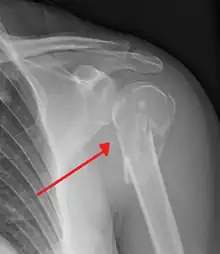

The axillary nerve is located at the proximal end, against the shoulder girdle. Dislocation of the humerus's glenohumeral joint has the potential to injure the axillary nerve or the axillary artery. Signs and symptoms of this dislocation include a loss of the normal shoulder contour and a palpable depression under the acromion.

Fracture of the proximal humerus